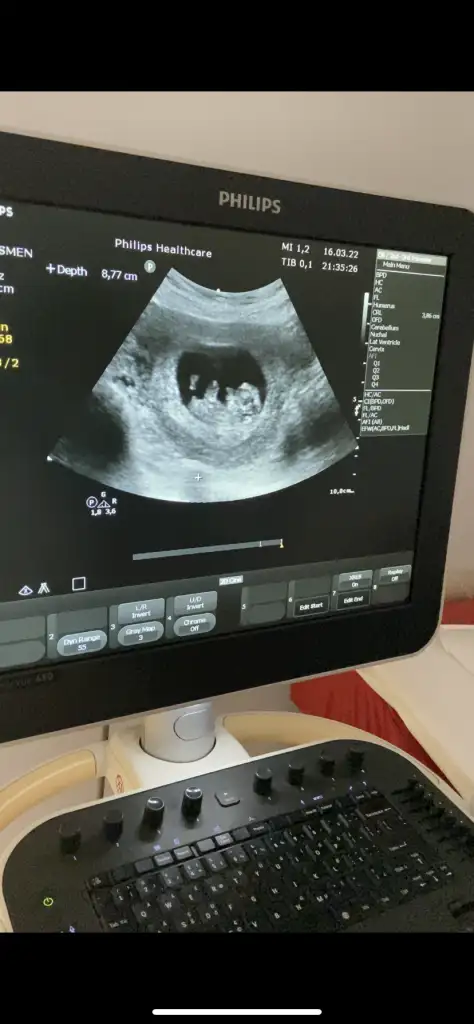

İkili test için çikolata yedim muayeneden yarım saat önce ilk lokmayı aldım gidene kadar bir paket bitti, kliniğe gidince su içip, yürüyüş yapmam istendi, bı bes on dk da yürüdüm. Sonuç, bebiş fazla hareketli olunca görüntü alınamadıİkili test için de hareketli olması lazımmış sanırım, aklımda bulunsun öyle yapayım bende en son çikolata yiyip girmiştim karnımda toktu öylece duruyordu tam sonunda birden hareketlenmeye başlamıştı. Evet tahminde bulunuyorlar özellikle erkek olursa gösterirse falan herhalde, bir de 3 boyutlu muydu 4 mü onda bakıpta tahminde bulunabiliyorlarmis daha bana öyle hiç bakmadi bakalim

Bak burda da fazla hareket girmiş devreye:)İkili test için çikolata yedim muayeneden yarım saat önce ilk lokmayı aldım gidene kadar bir paket bitti, kliniğe gidince su içip, yürüyüş yapmam istendi, bı bes on dk da yürüdüm. Sonuç, bebiş fazla hareketli olunca görüntü alınamadıüzerine on dk oturarak bekledim poz verdi miniğim

Biraz bu miniklerinde keyfine bağlı herhaldeİkili test için çikolata yedim muayeneden yarım saat önce ilk lokmayı aldım gidene kadar bir paket bitti, kliniğe gidince su içip, yürüyüş yapmam istendi, bı bes on dk da yürüdüm. Sonuç, bebiş fazla hareketli olunca görüntü alınamadıüzerine on dk oturarak bekledim poz verdi miniğim

Maşallah bi de meyve suyu diyorlar şekerden dolayı herhaldeBen girmeden yarım saat önce fıstıklı çikolata yemiştim kudur kudur kudurdu benim ki daha 10+2 günlüktü yeri de bol baya hareket etti

Ben ikili test yaptırmadım ama ilk 3 Aydan sonra detaylı organ muayenesi yaptı gibi bir şey oldu, tüm organlarına bakıyor anlatıyor herhangi bir sorun olup olmadığını söylüyor. Aynı zamanda plesantaya rahmin duruşuna rahim içi kan akışına falan hepsine bakıyor totalde bi 20 dk falan sürmüştür.

Benim rahmim ters olduğu İçin de biz çok net görüntü alamadık, sonra gittim bir şeyler yiyip yürüdüm doktorum vajinal bakmak istedi net görüntü almak İçin. Hatta eşim de vardı sordum rahatsız olur musun diye yok dedi:)

Rahimdeki görüntü inanılmaz net ve daha büyük oluyor bu arada.